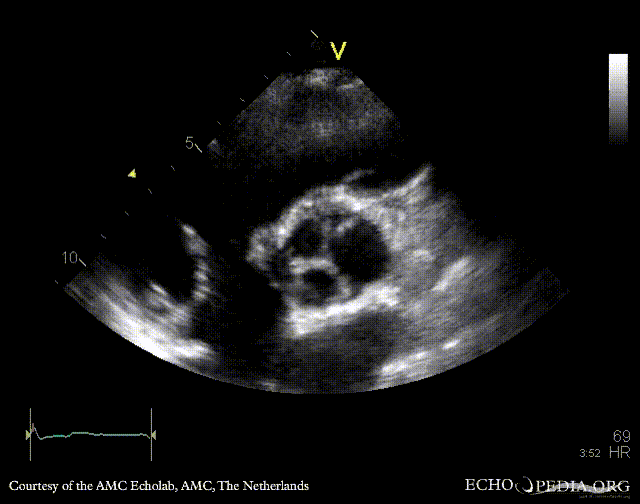

E00335.gif E00336.gif

PLAX: bicuspid aortic valve, doming of aortic valve PLAX: Color Doppler, mild aortic regurgitation